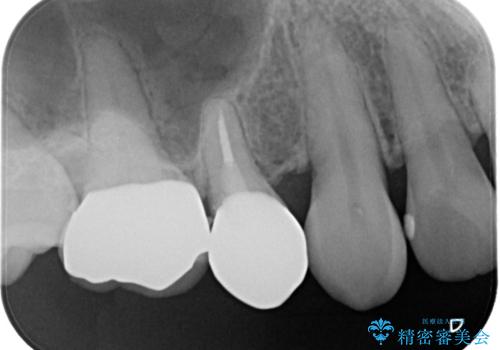

セラミックインレーを除去したところ、残存歯質が少なく破折のリスクを説明し、オールセラミッククラウン(スタンダード)でのやり替えとなりました。

オールセラミッククラウンの膨隆で下部鼓形空隙を適切な大きさに調整しました。